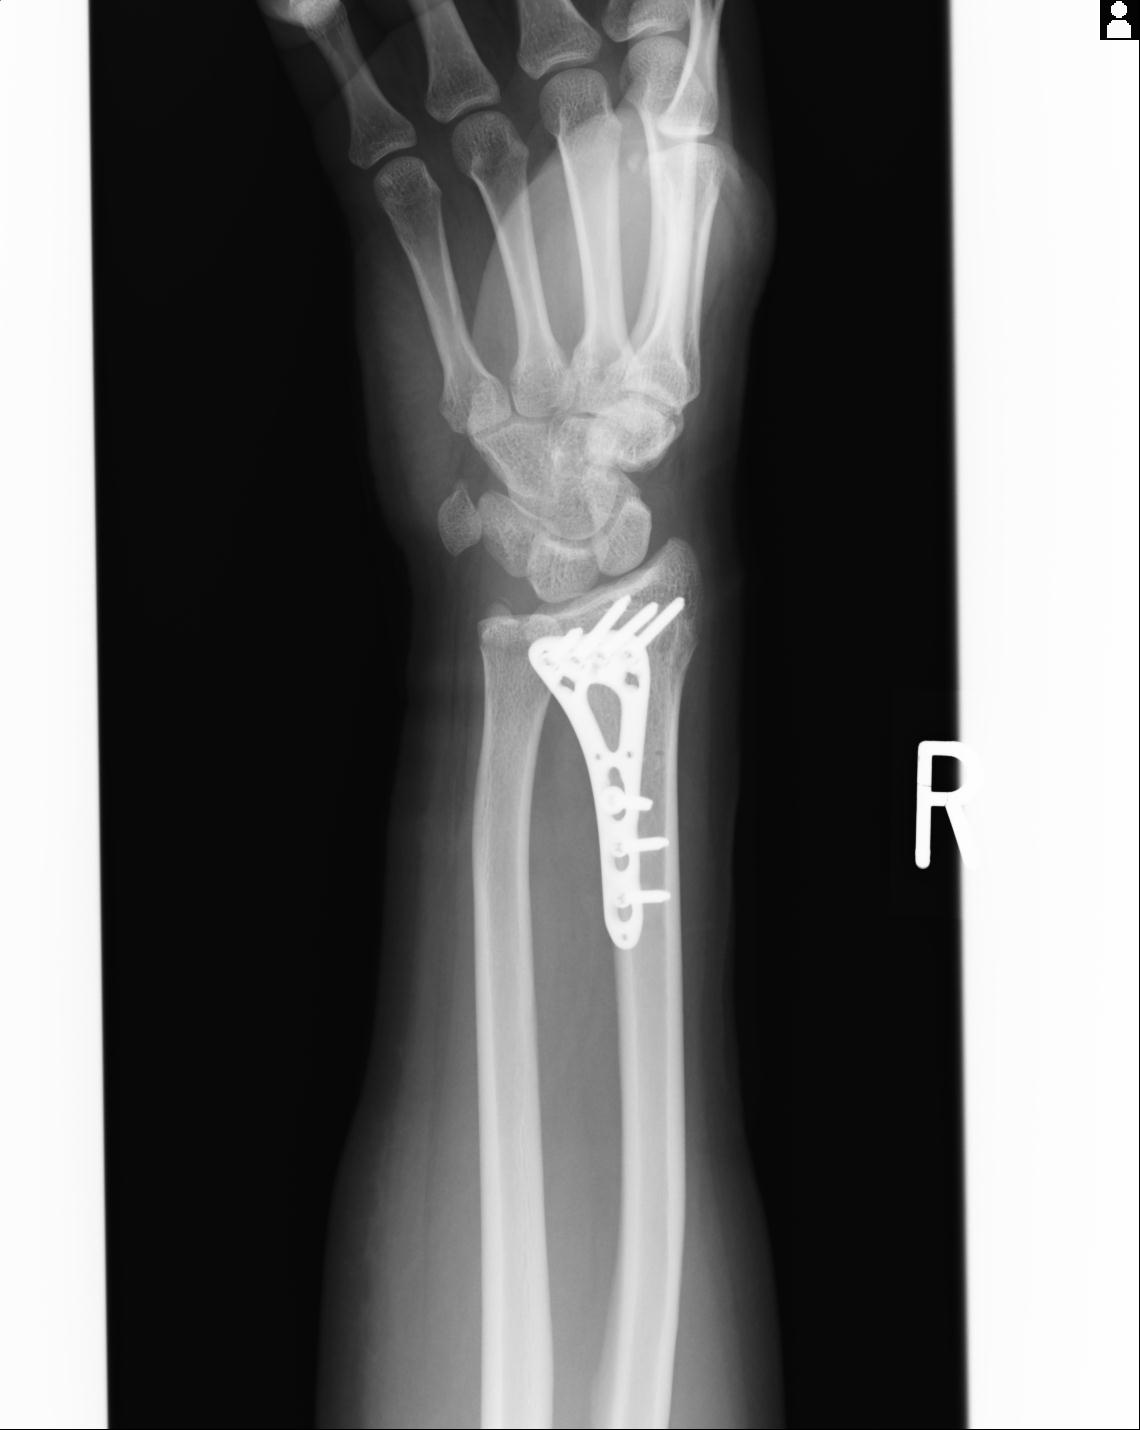

46666 1/23 両股正面+軸と右手関節 2R 76歳女性 右橈骨遠位端

102766 1/5 1/12 左手関節 4R 28歳男性 左橈骨遠位端

50435 1/4 1/15 手関節 4R 17歳女性 右橈骨遠位端

102739 12/30 1/5 左手関節 4R 92歳女性 橈骨遠位端

101290 1/4 5/21 5/20 手関節 2R 17歳男性 橈骨遠位端